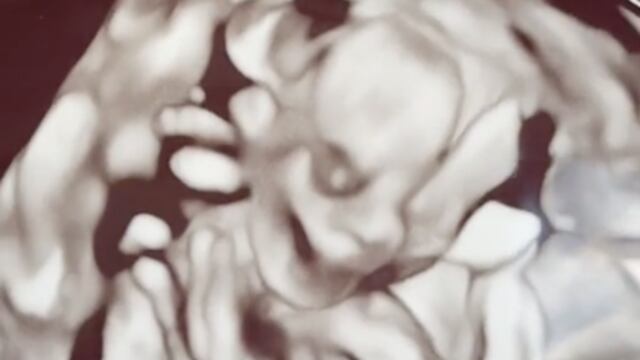

El video de TikTok, viralizó el momento en que unos padres se asustaron al ver la fotografía de ultrasonido de su bebé. El video abre con la frase “No lo recomiendo”.

En la descripción del video se observa el siguiente anuncio que junto a la frase se lee “No lo recomiendo si quieres tener miedo de tú bebe, obtenga una imagen de 3D en la semana 20″.

Quizás al niño no le asustará, pero a los padres les dará pesadillas y por eso a los padres les causó risa.

Algunos usuarios en los comentarios del video han comparado la fotografía bebé con el antihéroe de Spider-man: “Venom😂”, mientras otros lo han nombrado el mismísimo Lucifer: “Felicidades, ¿será un niño o niña demonio?😊😊”

Sin embargo, también hay quienes han señalado que la fotografía del ultrasonido está mal realizada le echan la culpa al técnico.

Aquí en este momento fue que los padres solicitaron la escalofriante fotografía de su bebé.